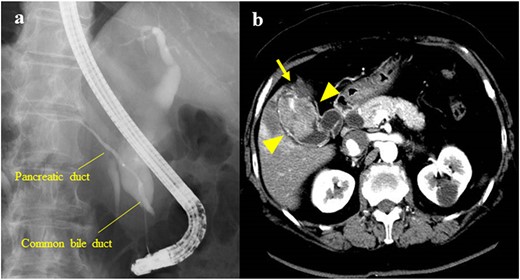

The patient was a 61-year-old woman who was diagnosed with PBM with Type Ic CBD. At 3 years before her presentation, the largest diameter of the common bile duct observed on endoscopic retrograde cholangiopancreatography (a procedure performed if choledocholithiasis is suspected) was 17 mm (Fig. 1a). After the diagnosis, the patient refused treatment and underwent follow-up observation alone. She was asymptomatic and did not visit the hospital regularly. However, at 3 years after the diagnosis of PBM, gallbladder cancer was detected on contrast-enhanced computed tomography (CECT), which was performed as a part of the PBM examination. The patient had a previous medical history of hypertension. Laboratory examinations revealed the following results: C-reactive protein, 2.29 mg/dl; alanine aminotransferase, 43 U/l; gamma-glutamyltransferase, 109 U/l; carcinoembryonic antigen, 4.0 ng/ml and carbohydrate antigen 19–9, 10 U/ml. At her most recent health examination, CECT revealed a 47-mm mass with a contrast effect in the gallbladder and liver invasion despite the absence of a mass 3 years previously (Fig. 1b). The patient then underwent extrahepatic bile duct resection, cholecystectomy, S4a/S5 hepatectomy and regional lymph node dissection. The liver-invading tumor was exposed on the surface, but it did not directly infiltrate into the other organs (Fig. 2a). The amylase level in the bile sample collected from the common bile duct was 136 400 U/l. A pathological examination revealed moderately differentiated adenocarcinoma of the gallbladder without bile duct involvement (T3aN0M0 Stage IIIa) (Fig. 2b). The post-operative course was uneventful, and gemcitabine and cisplatin therapy were administered as adjuvant chemotherapy for 8 months. However, liver and lung metastases developed 8 months after surgery, and the patient died 2 years after surgery.

(a) Endoscopic retrograde cholangiopancreatography showing PBM with a Type Ic CBD; the largest diameter of the common bile duct was 17 mm; (b) CECT showing a 47-mm mass with a contrast effect on the gallbladder (arrowhead); the tumor had invaded the S4a/S5 of the liver (arrow).